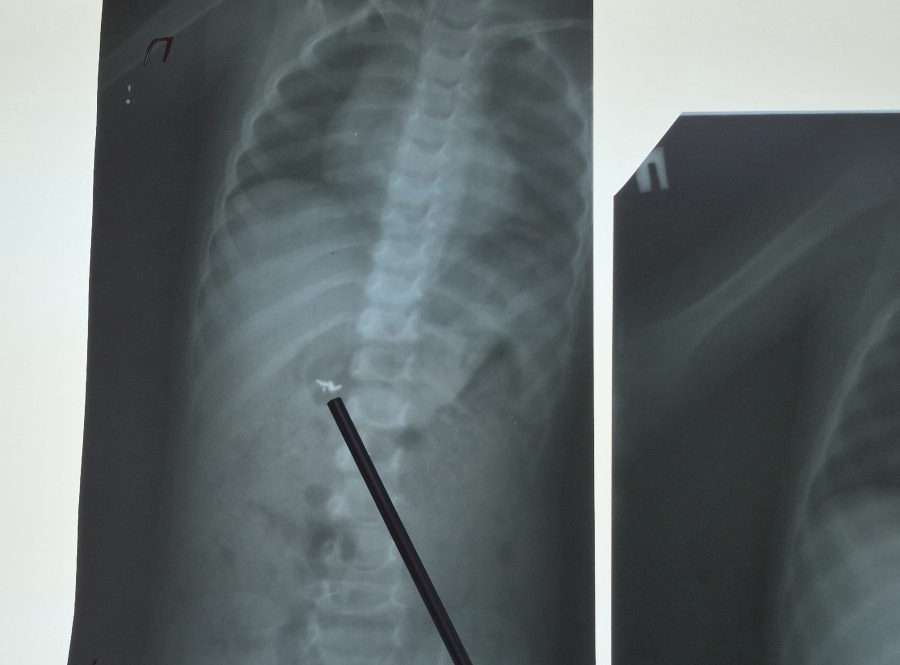

Родители привезли ребенка в Хвалынскую больницу для проведения рентгеновского исследования. Обследование выявило наличие постороннего предмета в желудке маленького пациента. После этого его направили в Балаковскую клиническую больницу (БГКБ) для дальнейшего лечения.

Контрольный рентгеновский снимок показал, что инородное тело состоит из трех частей и что они уже не находятся в желудке, а равномерно распределились по кишечнику.